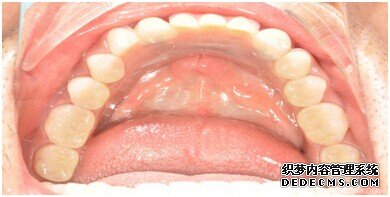

刘女士牙齿拍片初步检查

由CT片检查来看,刘女士口腔健康环境还是很好的,牙槽骨也适合种植牙的条件,而且由我们最后一颗牙是非常重要的,经过专家的建议和详细解释了原因之后,刘女士选择了美国百康种植牙。